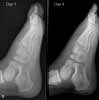

In the hospital. The pediatrician makes a presumptivediagnosis of cellulitis, admits the patient to the hospital,and initiates therapy with intravenous cefazolin, 50 to100 mg/kg/d divided every 6 hours. Figure 5 shows thepatient's foot 36 hours after the start of antibiotic therapy.Examination reveals increased swelling and tendernessover the dorsal surface; no fluctuance is present. Althoughcellulitis may not respond clinically to intravenous antibiotictherapy for up to 48 hours after its initiation, the patient'sincreasing foot pain prompts repeated laboratoryexamination.